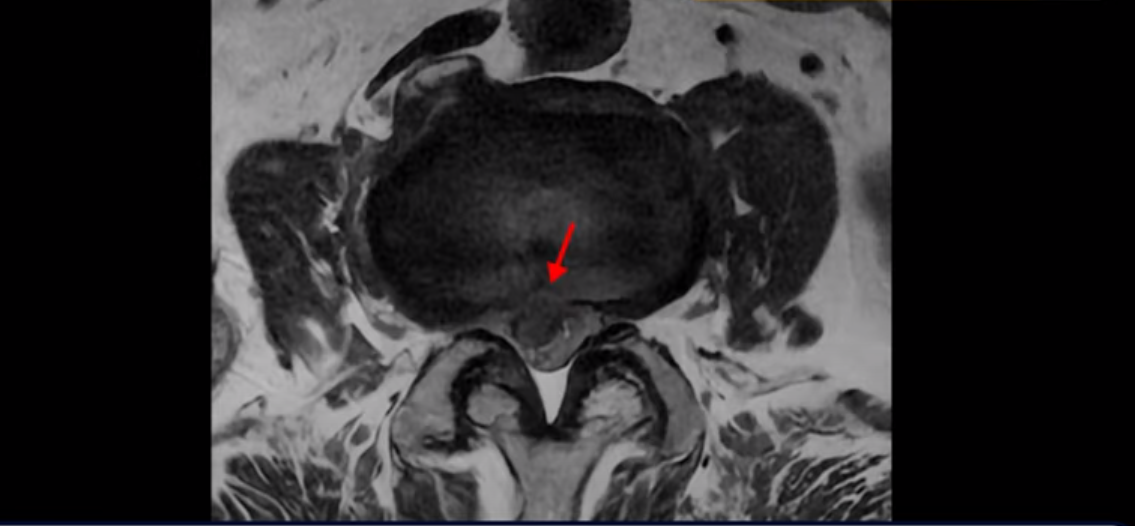

MRI를 보면 허리 4마디가 심하게 퇴행되어 있고

3번 뼈는 넘어질 때 생긴 압박골절이 있습니다.

3번 4번에는 척추관협착과 디스크 탈출이 보이고

4번 5번에는 척추관협착과 심한 디스크 파열이 있습니다.

5번 1번에는 뼈가 자라난 골극이 있고

기립근의 지방화도 심합니다. 또 3번 4번 마디에서는 신경가지가 빠져나가는 추간공이 왼쪽, 오른쪽 모두 많이 좁아져 있습니다.

이런 이유로 이 환자분은 왼쪽 다리는 마비가 생겨 힘이 빠지고 오른쪽 다리에는 심한 방사통이 있어서 휠체어까지 타야 하는 상태가 되었습니다. 이렇게 심하니까 대학병원에서 여러 마디 나사를 박는 유합술을 권유 받으셨는데요.